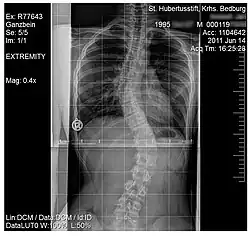

.jpg)

Scoliosis, is a medical condition where a person's spine has several irregular curves that are located between the neck and the pelvis.[8] Symptoms of scoliosis in mild cases usually exhibit abnormal posture, back pain, tingling or numbness in the legs and in worse cases can exhibit breathing problems, fatigue, permanent deformities and in rare cases heart problems.[8]